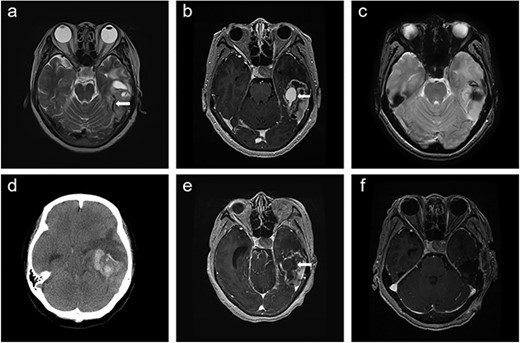

A 66-year-old woman presented with progressive cognitive deterioration and dysarthria. Non-contrast-enhanced brain magnetic resonance imaging (MRI) showed a 6-cm intraaxial mass in the left temporal lobe abutting the dura and an incidentally identified pituitary mass (Fig. 1a).

Time course of brain images during intratumoral hemorrhage formation; (a) initial T2-weighted image showing the tumor-draining vein without venous ectasia (arrow); (b, c) T1-enhanced image and gradient-echo image obtained 1 week after the initial MRI showing new-onset venous ectasia (arrow) without internal thrombus; (d, e) non-contrast-enhanced brain CT and T1-enhanced images obtained 1 day after images; (b) and (c) showing intratumoral hemorrhage with an intra-luminal thrombus (arrow); (f) post-operative T1-enhanced image.

Physical examination revealed global dysphagia accompanied by mild cognitive decline. The results of preoperative laboratory and coagulation tests were unremarkable. Gadolinium-enhanced brain MRI revealed lesion in the left temporal lobe exhibiting an irregular ring-enhancing component with central necrosis. Follow-up MRI showed new-onset venous ectasia of the tumor-draining vein into the transverse sinus, which was not observed on initial MRI (Fig. 1b). The draining vein joined the transverse sinus and narrowed at the confluence point. Gradient echo imaging showed that the lumen of the vein appeared patent without internal thrombus (Fig. 1c).

The next day, the patient experienced sudden headache and rapid consciousness deterioration. Brain computed tomography (CT) revealed acute hemorrhage inside the tumor with a midline shift (Fig. 1d). Navigational MRI showed that the contrast agent failed to fill the lumen of the venous dilatation (Fig. 1e).